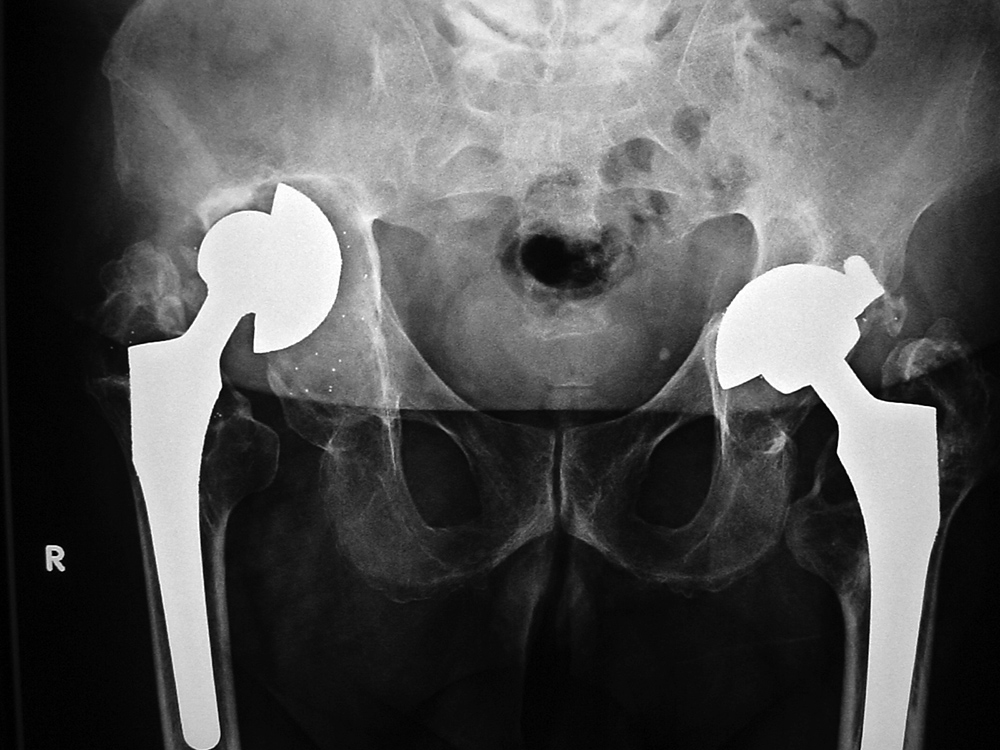

When local particulate matter becomes prominent and threatens or causes prosthesis failure, it is called particle disease or metallosis (figure: particle disease in right hip implant; figure: particle disease left hip CT; figure: left hip polyethylene liner wear; figure: metal-on-metal prosthesis with metallosis). See the discussion of adverse reaction to metal debris in Orthopedic medical devices and cross-sectional imaging: protocols and artifacts - MRI.

Metal-on-metal implants have become particularly controversial (figure: right hip metal-on-metal arthroplasty). DePuy voluntarily recalled the ASR XL metal-on-metal implant worldwide in 2010 because of a high revision rate (Ardaugh, 2013; FDA Hip Recalls). In the United Kingdom there was an approximate 13% revision rate for this device within 5 years. Two concerns have developed for metal-on-metal implants-somewhat high failure rates and possible systemic cobalt toxicity from high cobalt blood levels (figure: metal-on-metal prosthesis with metallosis). It appears that the greatest risk of systemic cobalt toxicity probably results from abnormal wear of a cobalt containing revision of a previously failed ceramic prosthesis instead of from primary failure of a metal-on-metal prosthesis (Bradberry, 2014). There is also data to suggest repeated measurement of metal ion (cobalt or chromium) levels does not provide useful information for clinical decision making (Reito, 2014).

| 29 year-old woman with bilateral hip dysplasia and placement of right metal-on-metal hip arthroplasty for advanced degenerative arthritis from the hip dysplasia. There is postoperative gas evident as well as a surgical drain. |

55 year-old woman |